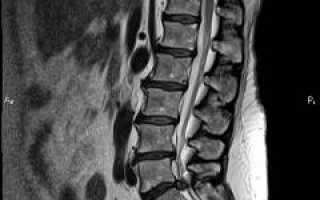

Межпозвоночную грыжу выявляет ортопед. Симптомы патологии подтверждаются инструментальными методами, среди которых магнитно-резонансная томография является «золотым стандартом». Этот метод позволяет определить локализацию и размеры грыжи, а также степень защемления спинномозгового нерва. Компьютерная томография также может быть использована, однако рентгенография не дает полной информации.

Для подтверждения смещения позвонков требуется консультация вертебролога или ортопеда. Учитываются клинические проявления и проводятся визуальные методы диагностики, такие как рентгенография и магнитно-резонансная томография. Эти методы позволяют оценить состояние позвонков и окружающих мягких тканей. При наличии нарушений в мышечной ткани может быть назначена электромиография.